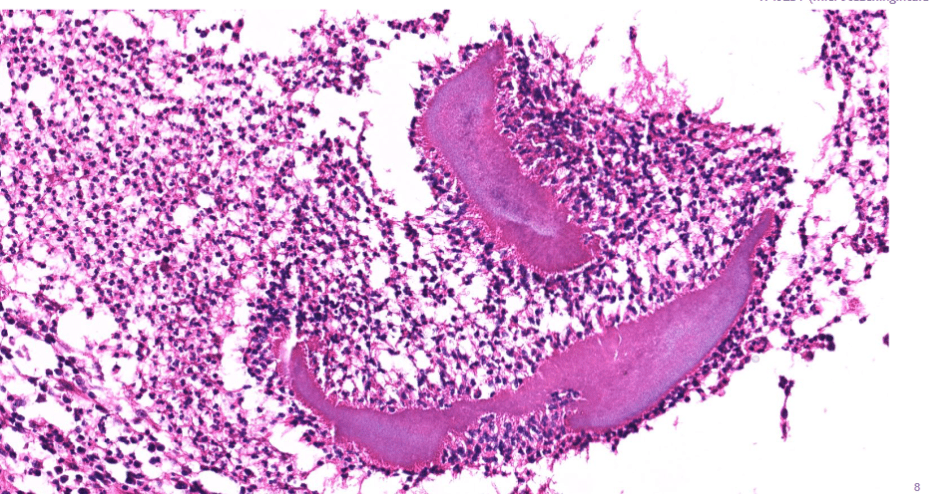

3. invaginated respiratory epithelium with cystic dilation

colon cancer